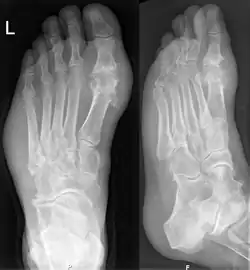

Guta poate fi diagnosticată și tratată fără investigații suplimentare la persoanele cu hiperuricemie și podagră clasică. Analiza lichidului sinovial trebuie făcută dacă există dubii asupra diagnosticului.[4] Razele X, deși sunt folositoare pentru a identifica guta cronică, nu au utilitate pentru atacurile acute de gută.[9]